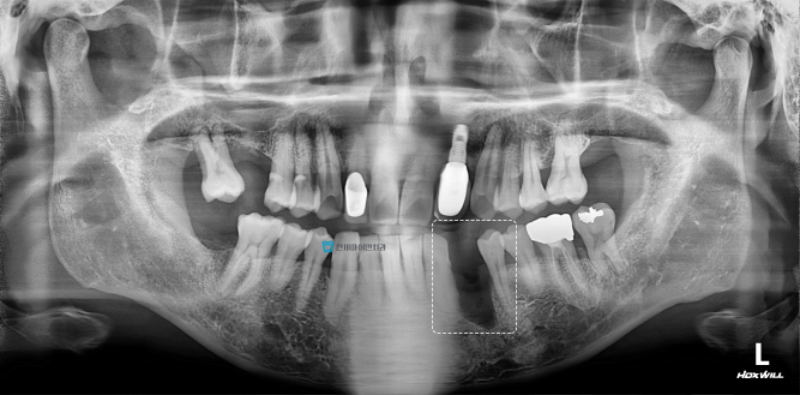

5.gif

왼쪽 아래 송곳니 발치 후 잇몸뼈가 부족해

임플란트가 불가능하다는 진단을 받고 내원하신 분입니다.

파노라마에서도 해당 부위 잇몸뼈가 많이 흡수된 것을 볼 수 있습니다.